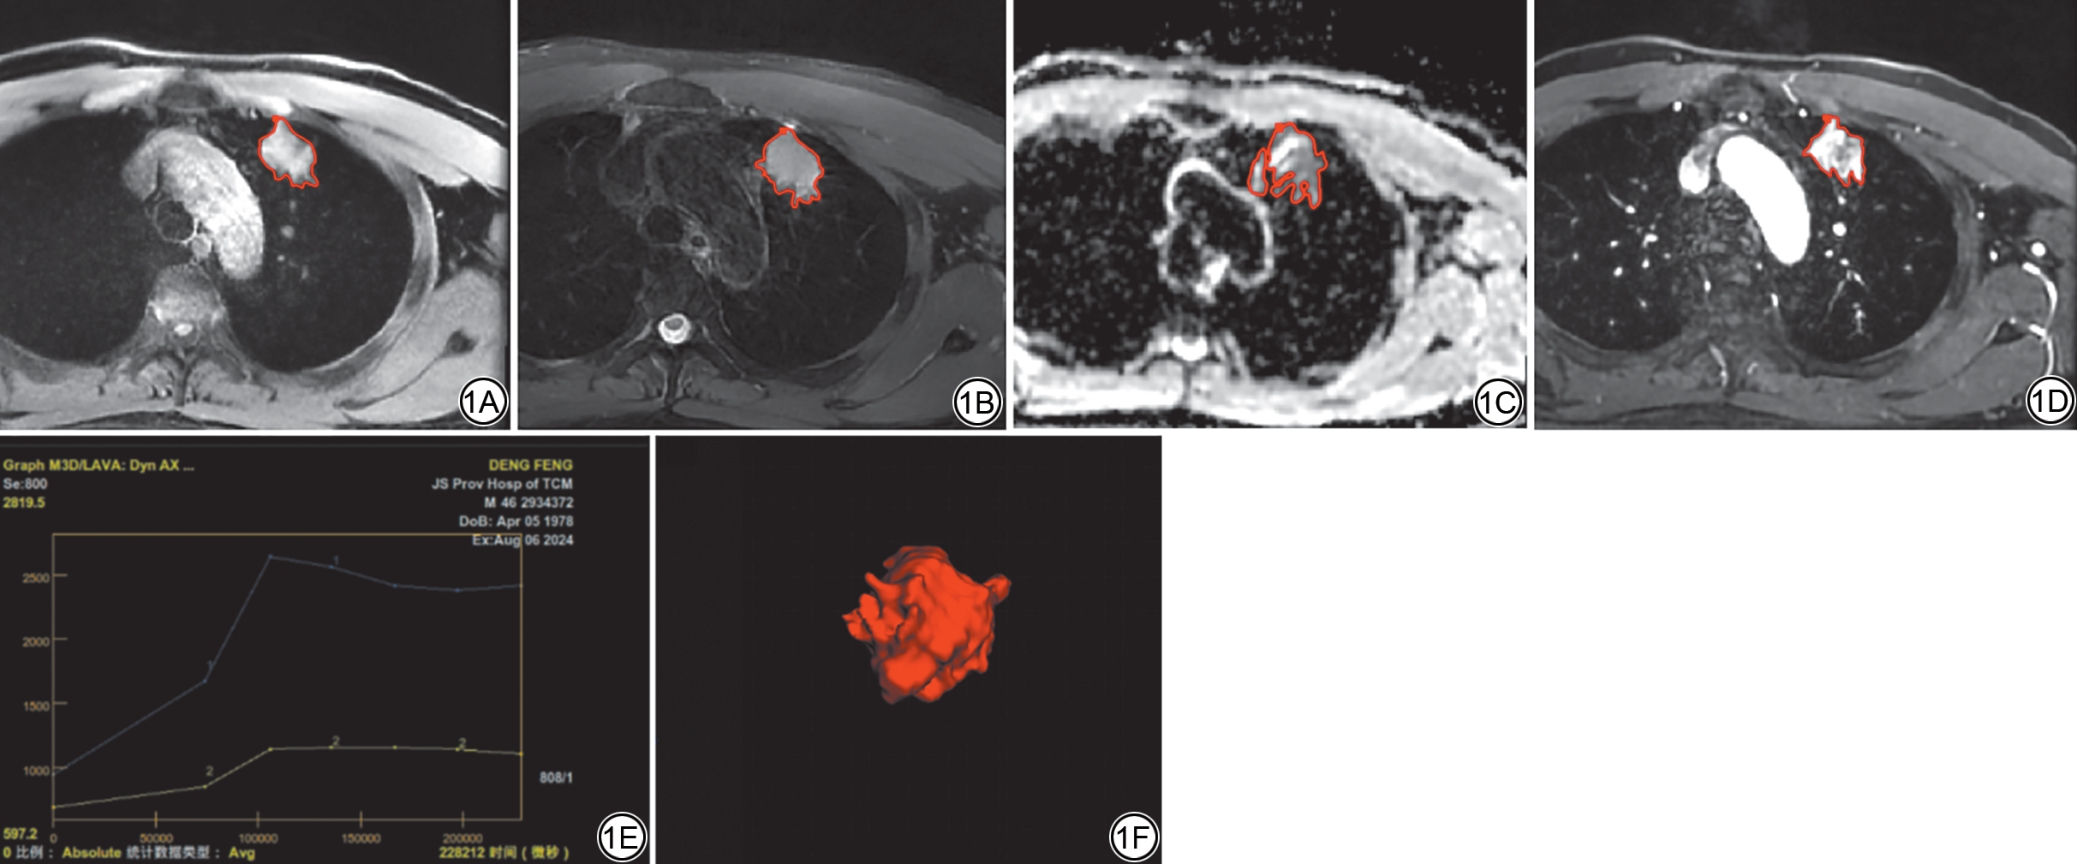

DCE-MRI图像中选取TIC峰值点对应时相作为影像组学特征提取的目标图像[20]。将患者T1WI、T2WI、ADC和DCE-MRI各序列原始图像导入Python(Version:3.13.5,https://www.python.org/),由DICOM格式转换为NIfTI格式(压缩为.nii.gz文件),然后对图像进行预处理,包括:体素标准化(1 mm3)、线性插值重采样、高斯滤波去噪及灰度离散化。将预处理后的图像分别导入ITK-SNAP软件(Version:3.8.0, https://www.itksnap.org/)中,设置窗宽为500,窗位为50,以便更清晰地勾画病灶区域。由一名研究生与一名主治医师(5年经验)分别独立使用该软件,沿肿瘤边缘手动逐层勾画感兴趣区(region of interest, ROI),在病灶勾画过程中主动规避主要血管及支气管结构(图1)。对于勾画不一致的病例,则邀请一位具有25年胸部影像诊断经验的主任医师仲裁,最终协商达成一致。勾画操作的可重复性通过Dice系数进行评估。若同一病例中观察到多个病灶,则仅标记最大的病灶。

图1  病例勾画示意图。男,46 岁,肺腺癌患者。采用ITK-SNAP软件手动勾画ROI。1A:T1WI-FS 病灶ROI 勾画;1B:T2WI-FS 病灶ROI 勾画;1C:ADC图像病灶ROI 勾画;1D:DCE-MRI 图像病灶ROI 勾画;1E:TIC呈流出型,蓝色曲线代表肿块的强化模式,黄色曲线代表肌肉的强化模式;1F:融合T2WI-FS 序列多层ROI 后构建的三维肿瘤立体模型。红色曲线为病灶ROI。ROI:感兴趣区;T1WI-FS:T1 加权脂肪抑制成像;T2WI-FS:T2 加权脂肪抑制成像;ADC:表观扩散系数;DCE-MRI:动态对比增强磁共振成像;TIC:时间-信号强度曲线。

Fig. 1  Case illustration of lesion segmentation: A 46-year-old male patient with lung adenocarcinoma. Manual ROI delineation was performed using ITK-SNAP software. 1A: Delineation of ROIs on T1WI-FS; 1B: Delineation of ROIs on T2WI-FS. 1C: ROI delineation of the lesion on the ADC map. 1D: ROI delineation of the lesion on DCE-MRI. 1E: TIC shows a washout pattern. The blue and yellow curves depict the TIC of the mass and muscle, respectively. 1F: A three-dimensional tumor model constructed by fusing multi-layer ROIs from T2WI-FS sequences. The red curve is the ROI. ROI: region of interest; T1WI-FS: T1-weighted imaging with fat suppression; T2WI-FS: T2-weighted imaging with fat suppression; ADC: apparent diffusion coefficient; DCE-MRI: dynamic contrast-enhanced magnetic resonance imaging; TIC: time-intensity curve.